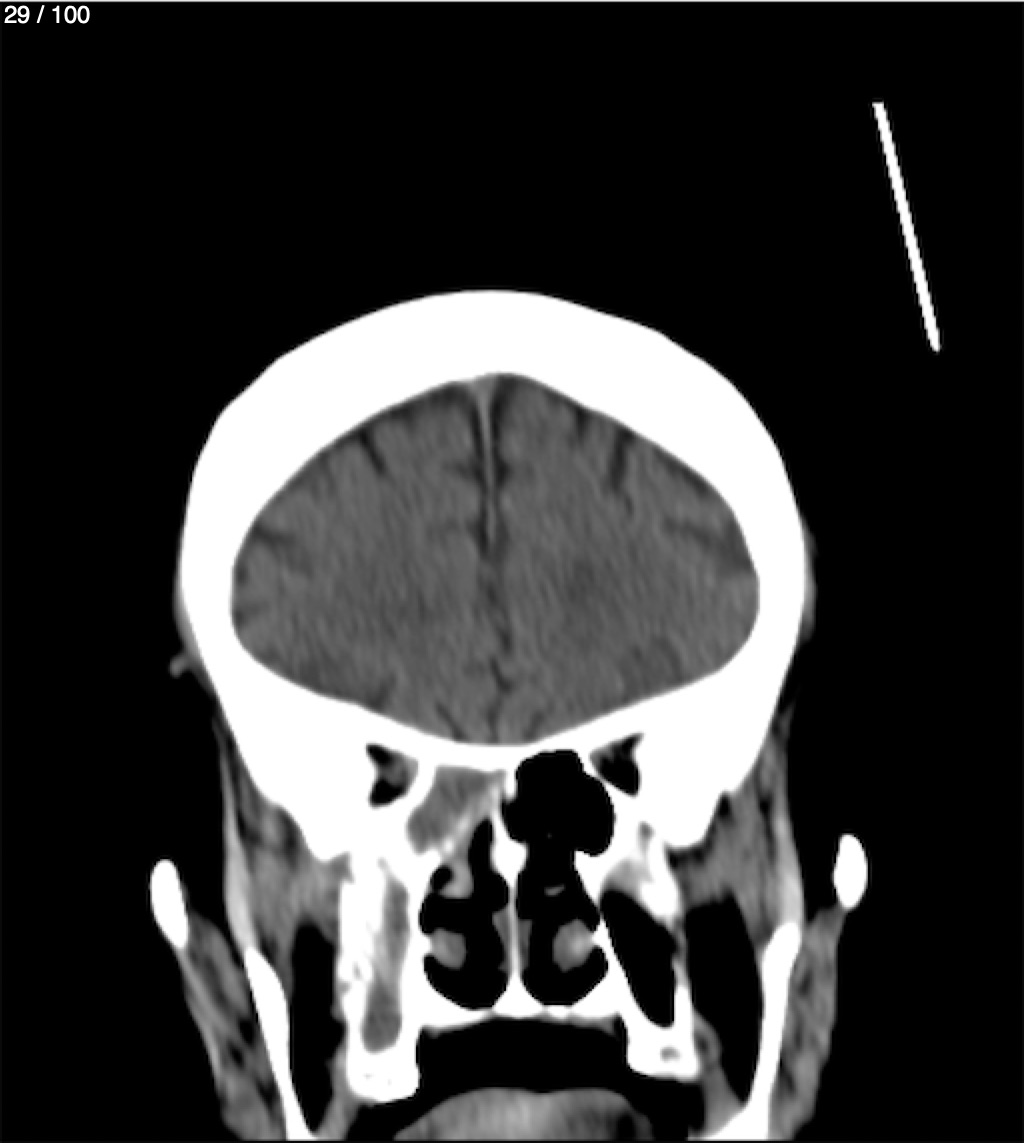

Jose Sosa Martinez 66A - Angiotac Craneo